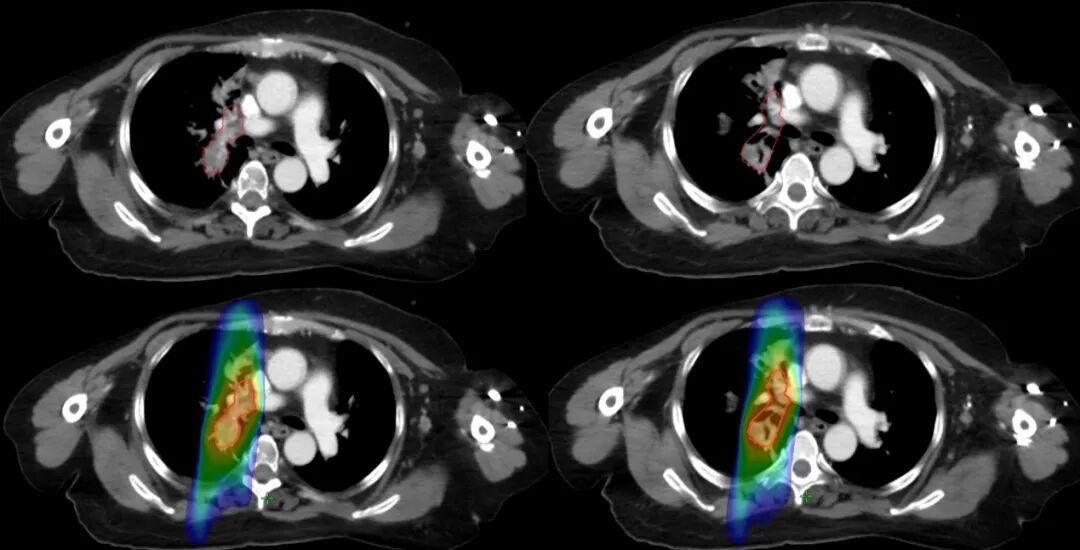

【學科風采】乳腺癌患者千里求醫(yī),成功治療多發(fā)腦轉移瘤、脊髓轉移、腦膜轉移、椎管內多發(fā)轉移結節(jié)、肺炎及肺門轉移患者